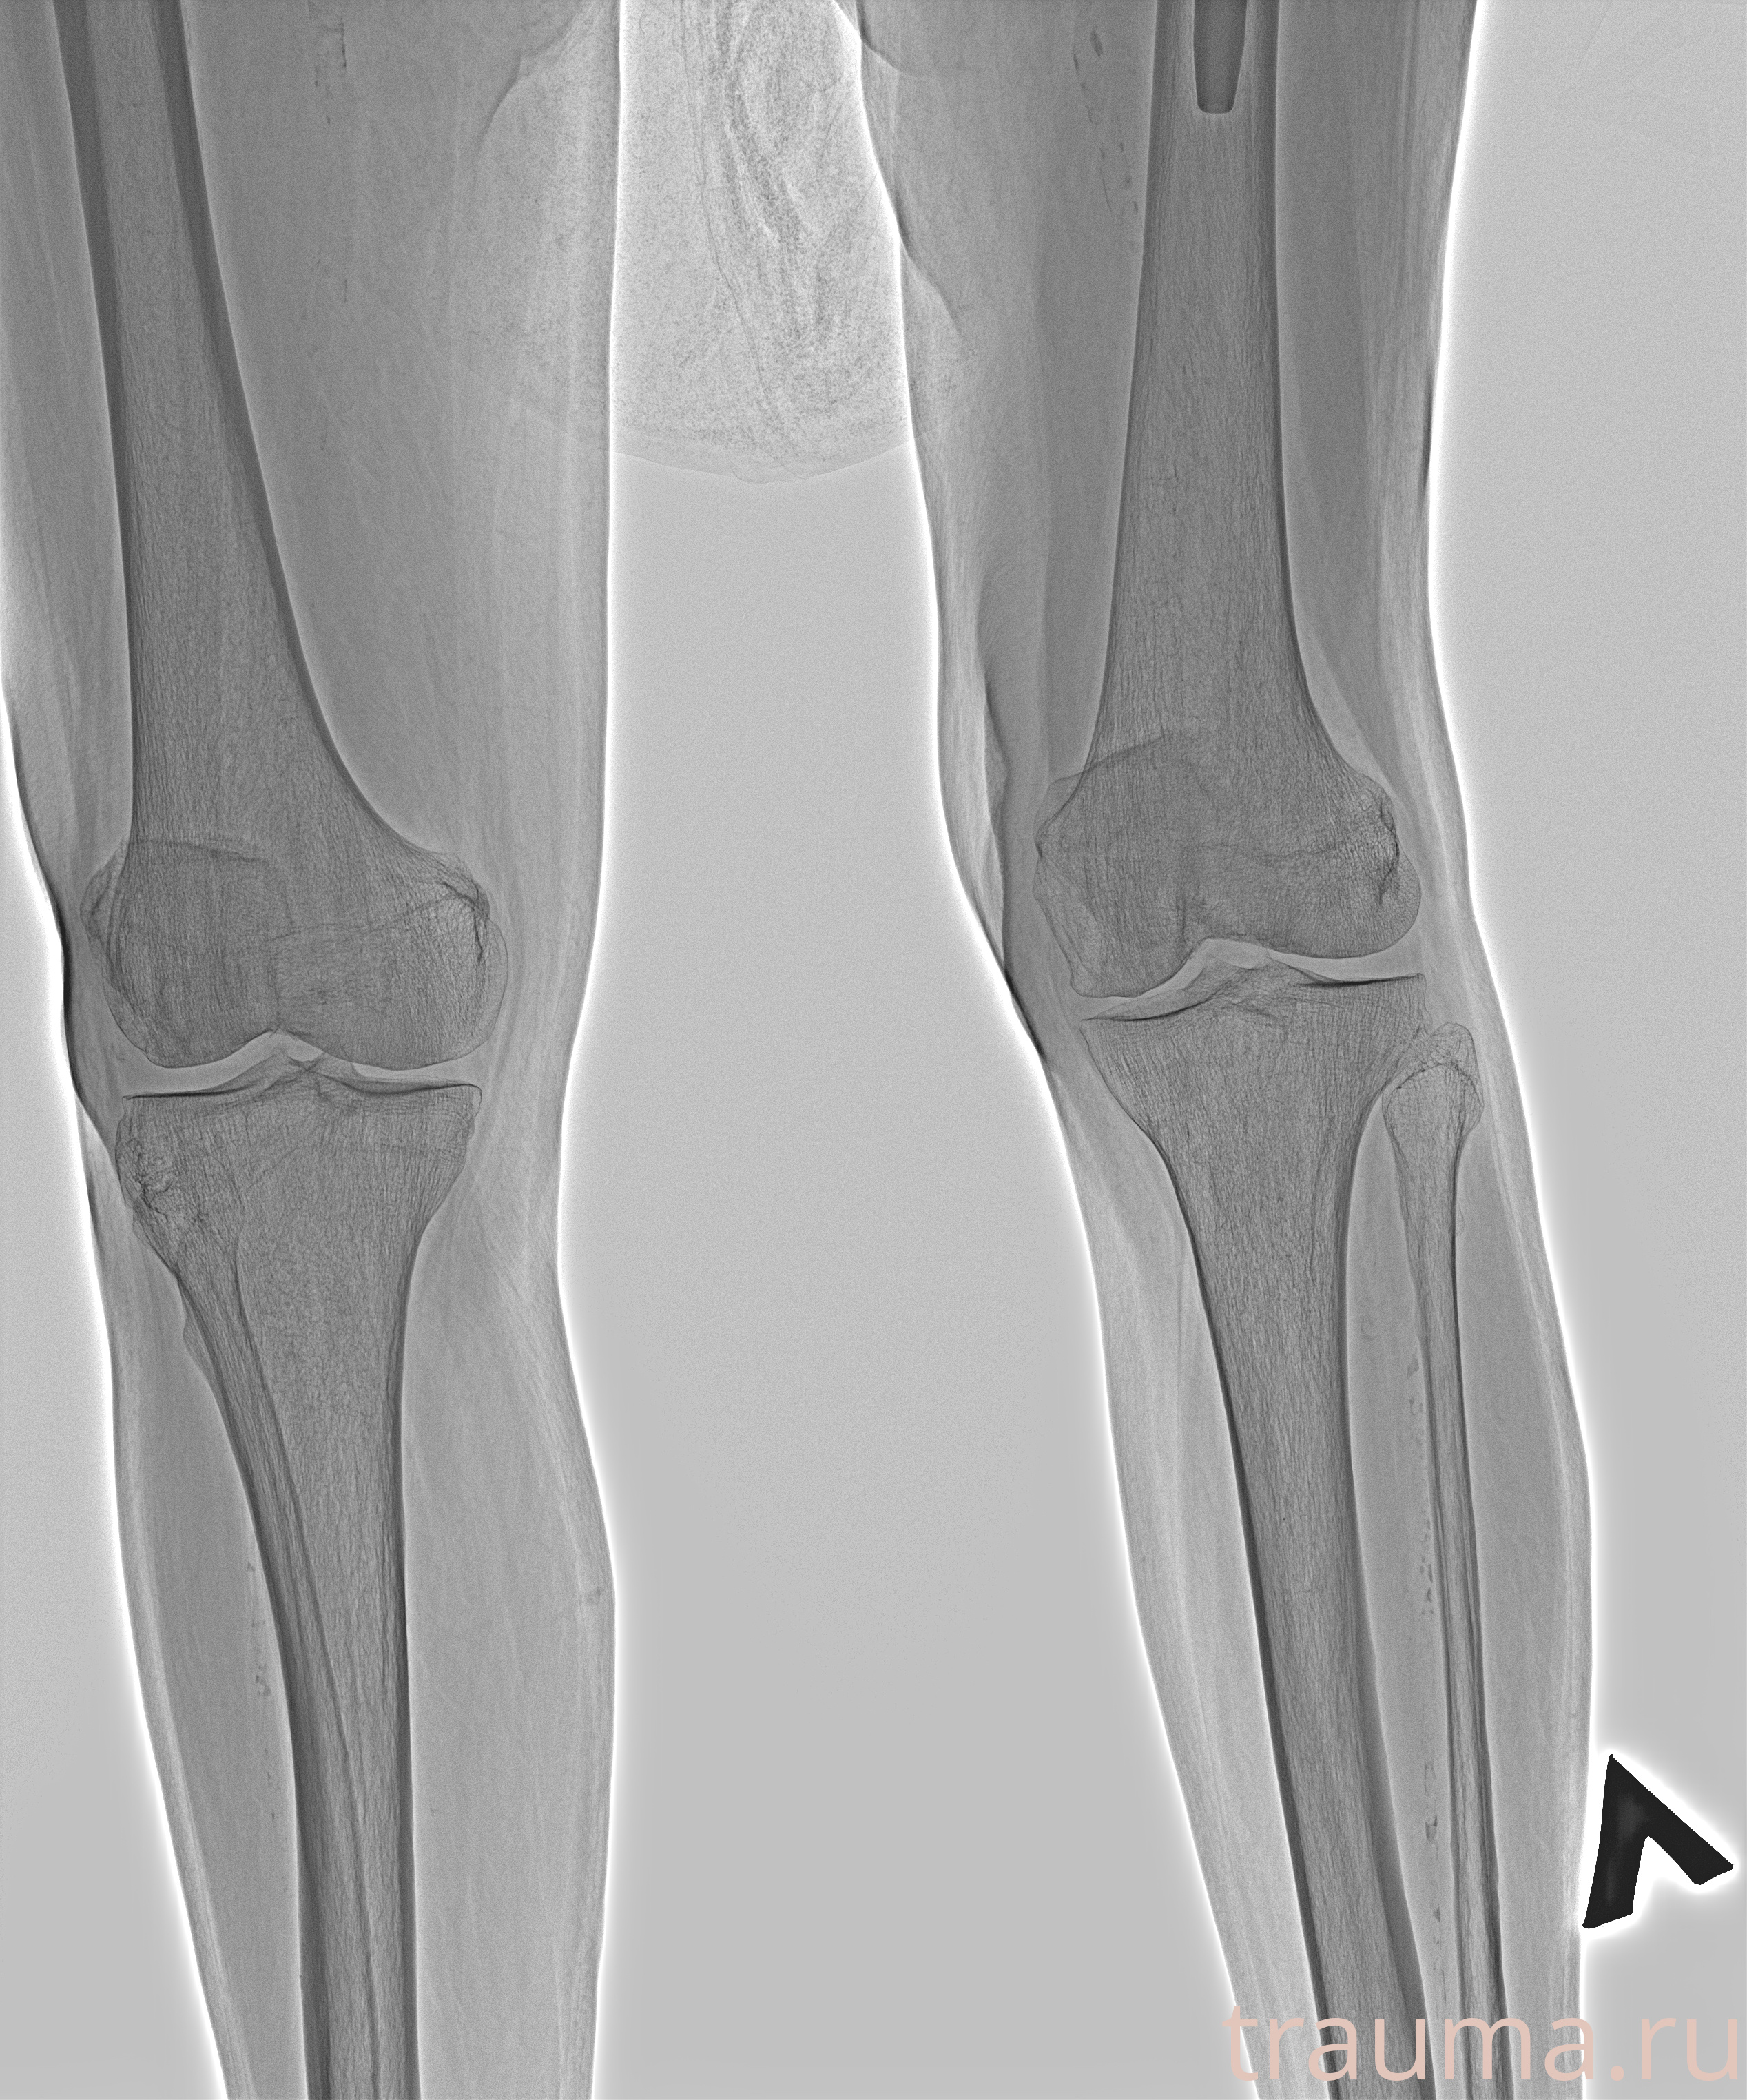

Рентгенограммы

Рентген на дому: по вашему адресу приезжает врач-рентгенолог, травматолог-ортопед с мобильным рентгеновским аппаратом, проводит диагностику травмы или заболевания, делает необходимые рентгенограммы, дает рекомендации по дальнейшему лечению. Получить качественные снимки в домашних условиях возможно благодаря уникальной методике, разработанной МосРентген Центром для института  Склифосовского